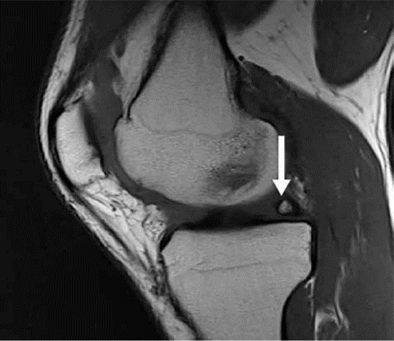

Hình 3. Hình ảnh cộng hưởng từ có trọng số mật độ proton sagital có sụn chêm bên dạng đĩa với tín hiệu tăng trong sụn.

Hình 6. Nốt sần sụn chêm. Hình ảnh pd sagittal cho thấy một nốt sần hình sụn (mũi tên) ở vùng của rễ sụn trung gian sừng sau.